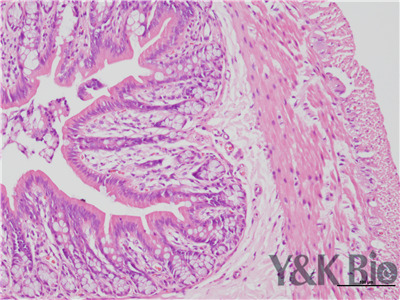

病理技术服务中HE染色法,学名苏木精-伊红染色,在法陕西石蜡切片技术里是经常用的染色法之一。石蜡切片常用于观察正常细胞组织的形态结构,是病理学用以研究、观察及判断细胞组织形态变化的主要方法。苏木精染液是碱性的 ,主要使细胞核内的染色质与胞质内的核糖体着紫蓝色 ;伊红为酸性的染料 ,主要使细胞质和细胞外基质中的成分着红色。HE染色法是组织学、胚胎、病理学教学与科研中基本、使用广泛的技术方法。

HE染色中要注意细胞核的分化程度,注意苏木素和伊红的效价,及时更换染液,一般实验周期为15个工作日。